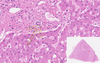

Fatty Liver Flashcards

1

Q

Name of the Slide?

A

Fatty Liver